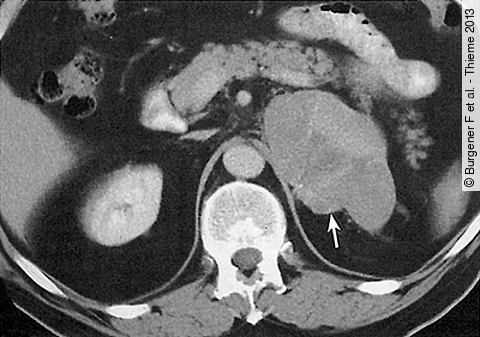

Sie sind selten, aber schlecht behandelbar: bösartige Tumore der Nebennieren. Eine neue europäische Leitlinie gibt jetzt erstmals Vorgaben für ihre Behandlung. Federführend bei der Entwicklung waren Würzburger Mediziner.